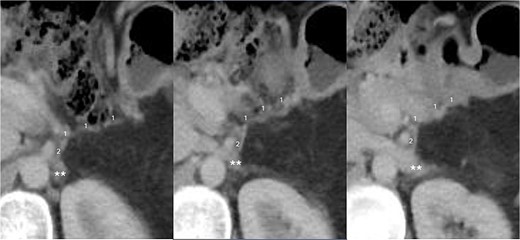

After excision of the tumor, persistent congestion of the lesser curvature and changes in the appearance of the posterior gastric wall, including petechiae and violet discoloration, were observed. To overcome this issue, adequate length of the LGV to reach the LAV to perform tension-free anastomosis was observed using a 6-0 polipropilene suture, which was approximated in a running fashion, and the anterior surface was performed using separate stitches. After unclamping, a significant reduction in congestion was observed; after 1 h, only the residual petechiae were observed. Previous varicose veins were found to have decreased in diameter (Fig. 2).

![Final intraoperative view after the RAMPS procedure. Left gastric vein [1], left adrenal vein [2], and vascular anastomosis (white arrowhead). Variceal veins at the level of the lesser curvature (*). Left renal vein (**).](https://oupdevcdn.silverchair-staging.com/oup/backfile/Content_public/Journal/jscr/2024/8/10.1093_jscr_rjae541/1/m_rjae541f2.jpeg?Expires=1772754036&Signature=Chk9rOPoTcvVDL0aZbidBNCk75Z8Us6-JqWp-cGH0UGUvgfCzg2g4mEAw33Yfcwb8Jy9fPGQ--esvIZ5f~dDVcLfMSX2HeoUA2E-xfWgq9sRFMOvUPGtz~r8XIAyLv286DKC47WqnL3Pa0zjJCdWhNVcZRSeJZloNArvZDjEvZ3nxEziKwyxM2poBUBszEyLzP~Kz9FTtF-5s7gxr0S7pGu429HoqJIuuwCUVWfhk1vxnbEW27rm1kvXBmcV0JvX4g6SZSOWSouZfupKj2hBS0j3azSEQKMVvyVFje4hCZQfLMuBBKm0h1IEJhAhuHAGpU9oNKt7GjHHQqbu52OQrA__&Key-Pair-Id=APKAIYYTVHKX7JZB5EAA)